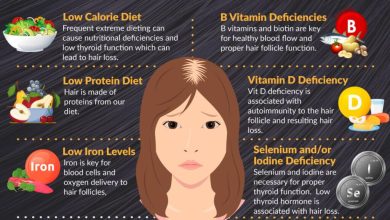

स्वास्थ्य विशेषज्ञ कहते हैं, गड़बड़ जीवनशैली डायबिटीज बढ़ने की सबसे बड़ी वजह है। लंबे समय तक एक ही जगह पर बैठे रहना, शारीरिक रूप से कम मेहनत करना, जंक फूड्स का अधिक सेवन और स्ट्रेस के कारण खतरा बढ़ा है। जिन लोगों का ब्लड शुगर अक्सर बढ़ा हुआ रहता है उनमें हार्ट, तंत्रिका, आंखों के साथ किडनी पर असर पड़ सकता है।

जिन लोगों को लंबे समय से डायबिटीज है उनमें यह खतरा अधिक होता है। इसके अलावा ब्लड प्रेशर हाई रहना, धूम्रपान और मोटापा की समस्या भी जोखिमों को बढ़ा देती है।

नमक का सेवन कम करना, धूम्रपान और अल्कोहल से दूरी बनाने के साथ रोजाना कम से कम 30 मिनट तेज वॉक करना भी जरूरी है। इसके साथ किडनी को स्वस्थ रखने के लिए आहार में हरी सब्जियां, साबुत अनाज, फाइबर युक्त फल जैसे सेब, अमरूद को शामिल करें। साल में कम से कम एक बार किडनी फंक्शन टेस्ट जरूर कराएं।